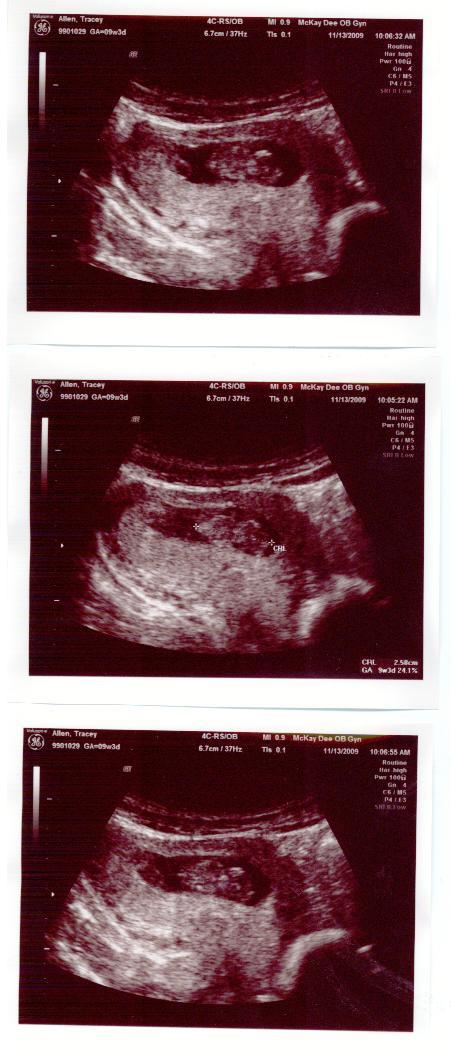

I finally got our ultrasounds into the computer! I'm such a procrastinator. Hey, nowbody is perfect. :] The ultrasound was done when I was 9 weeks and 3 days prego. The baby was 6.7 centimeters. So small. :] According to the Bump.com (i subscribed to get weekly updates) the baby is NOW the size of a lime and I am 11 weeks along. :] We are so excited to start our family. We hope it's a boy but we'll be just as happy with a girl. We've kind of thought of names but nothing has really triggered our fancy.